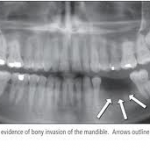

Diagnosis is hindered by the fact that X-rays (even digital and/or panoramic) often do not detect dental osteomyelitis. Add to that the absence of facial pain in most cases, the reluctance most dentists have in removing dead teeth, and the devastation people feel about losing their teeth, and we have millions of people in our culture with hidden dental infections.